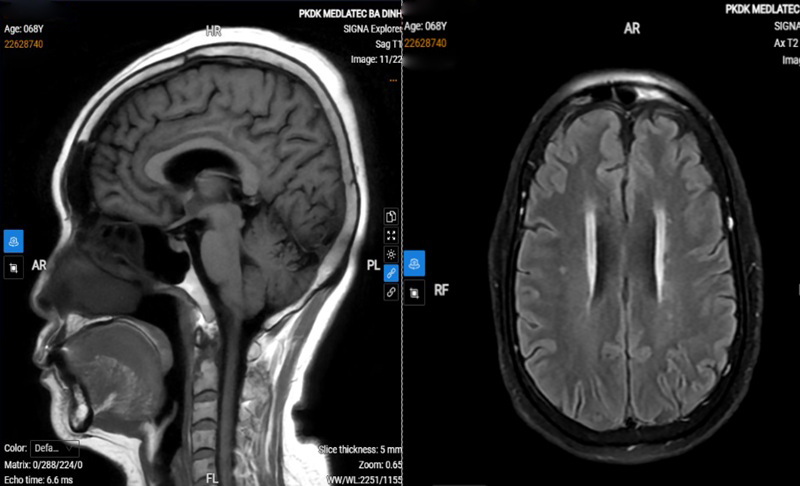

Người phụ nữ 60 tuổi ở Phú Thọ xuất hiện tình trạng đau đầu kéo dài kèm chóng mặt. Dù đã điều trị nội trú tại địa phương nhưng triệu chứng không cải thiện nên bà đến MEDLATEC thăm khám. Tại đây, các bác sĩ đã tìm ra nguyên nhân và điều trị cho bà theo đúng phác đồ.